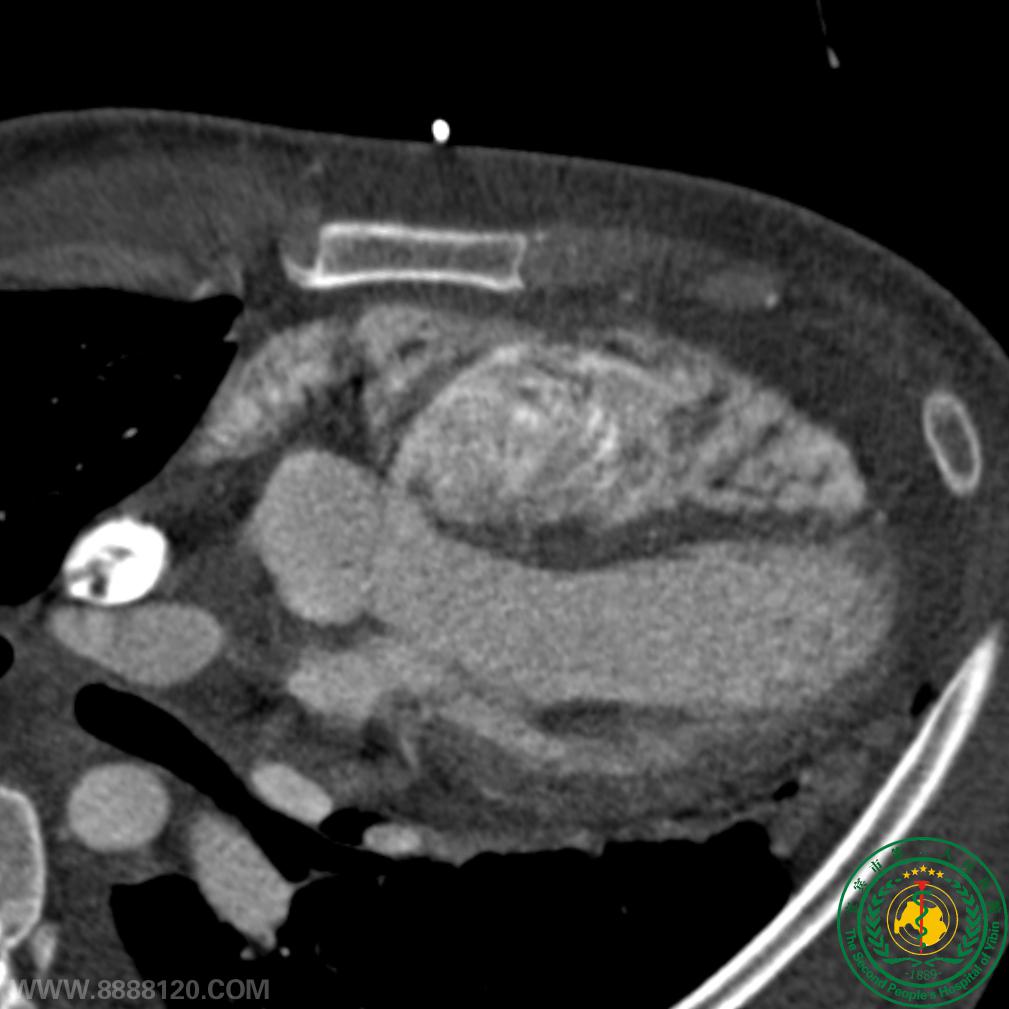

我院CT室推出胸部血管(冠状动脉、肺动静脉、主动脉)一站式检查技术

我院CT室推出胸部血管(冠状动脉、肺动静脉、主动脉)一站式检查技术5667